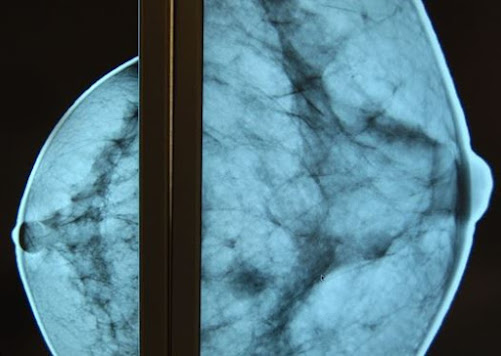

Peu connue par le grand public, la sénologie représente pourtant une spécialité médicale majeure dans les prises en charge de cancérologie. La sénologie permet de prévenir, dépister et soigner les pathologies du sein comme le cancer du sein. Le sénologue réalise des examens mammaires afin d’identifier les pathologies du ou de la patient(e) et de prescrire le traitement adapté.

Lors de ses consultations, le docteur FROMONT détermine les examens complémentaires nécessaires type mammographies ou biopsies permettant notamment d’affiner les options thérapeutiques et de proposer à la patiente la meilleure prise en charge adaptée. « En effet, la chirurgie n’est pas toujours le seul traitement possible et chaque cancer est unique. Nous devons donc déterminer la meilleure thérapie pour la patiente. Celle-ci est discutée en RCP (Réunion de Concertation Pluridisciplinaire) et peut inclure parfois de la radiothérapie et de la chimiothérapie. Dans tous les cas, dès l’annonce du diagnostic, nous mettons en place un parcours de soins complet et pluridisciplinaire autour de la patiente », indique Alice FROMONT.

Même si des gestes simples comme l’autopalpation mammaire sont essentiels, le docteur FROMONT insiste sur la prévention, notamment par la mammographie. « Notre région est aujourd’hui en retard, car encore trop peu de femmes en font régulièrement. C’est pourtant essentiel pour dépister un cancer au plus tôt et ainsi maximiser les chances de guérison ».